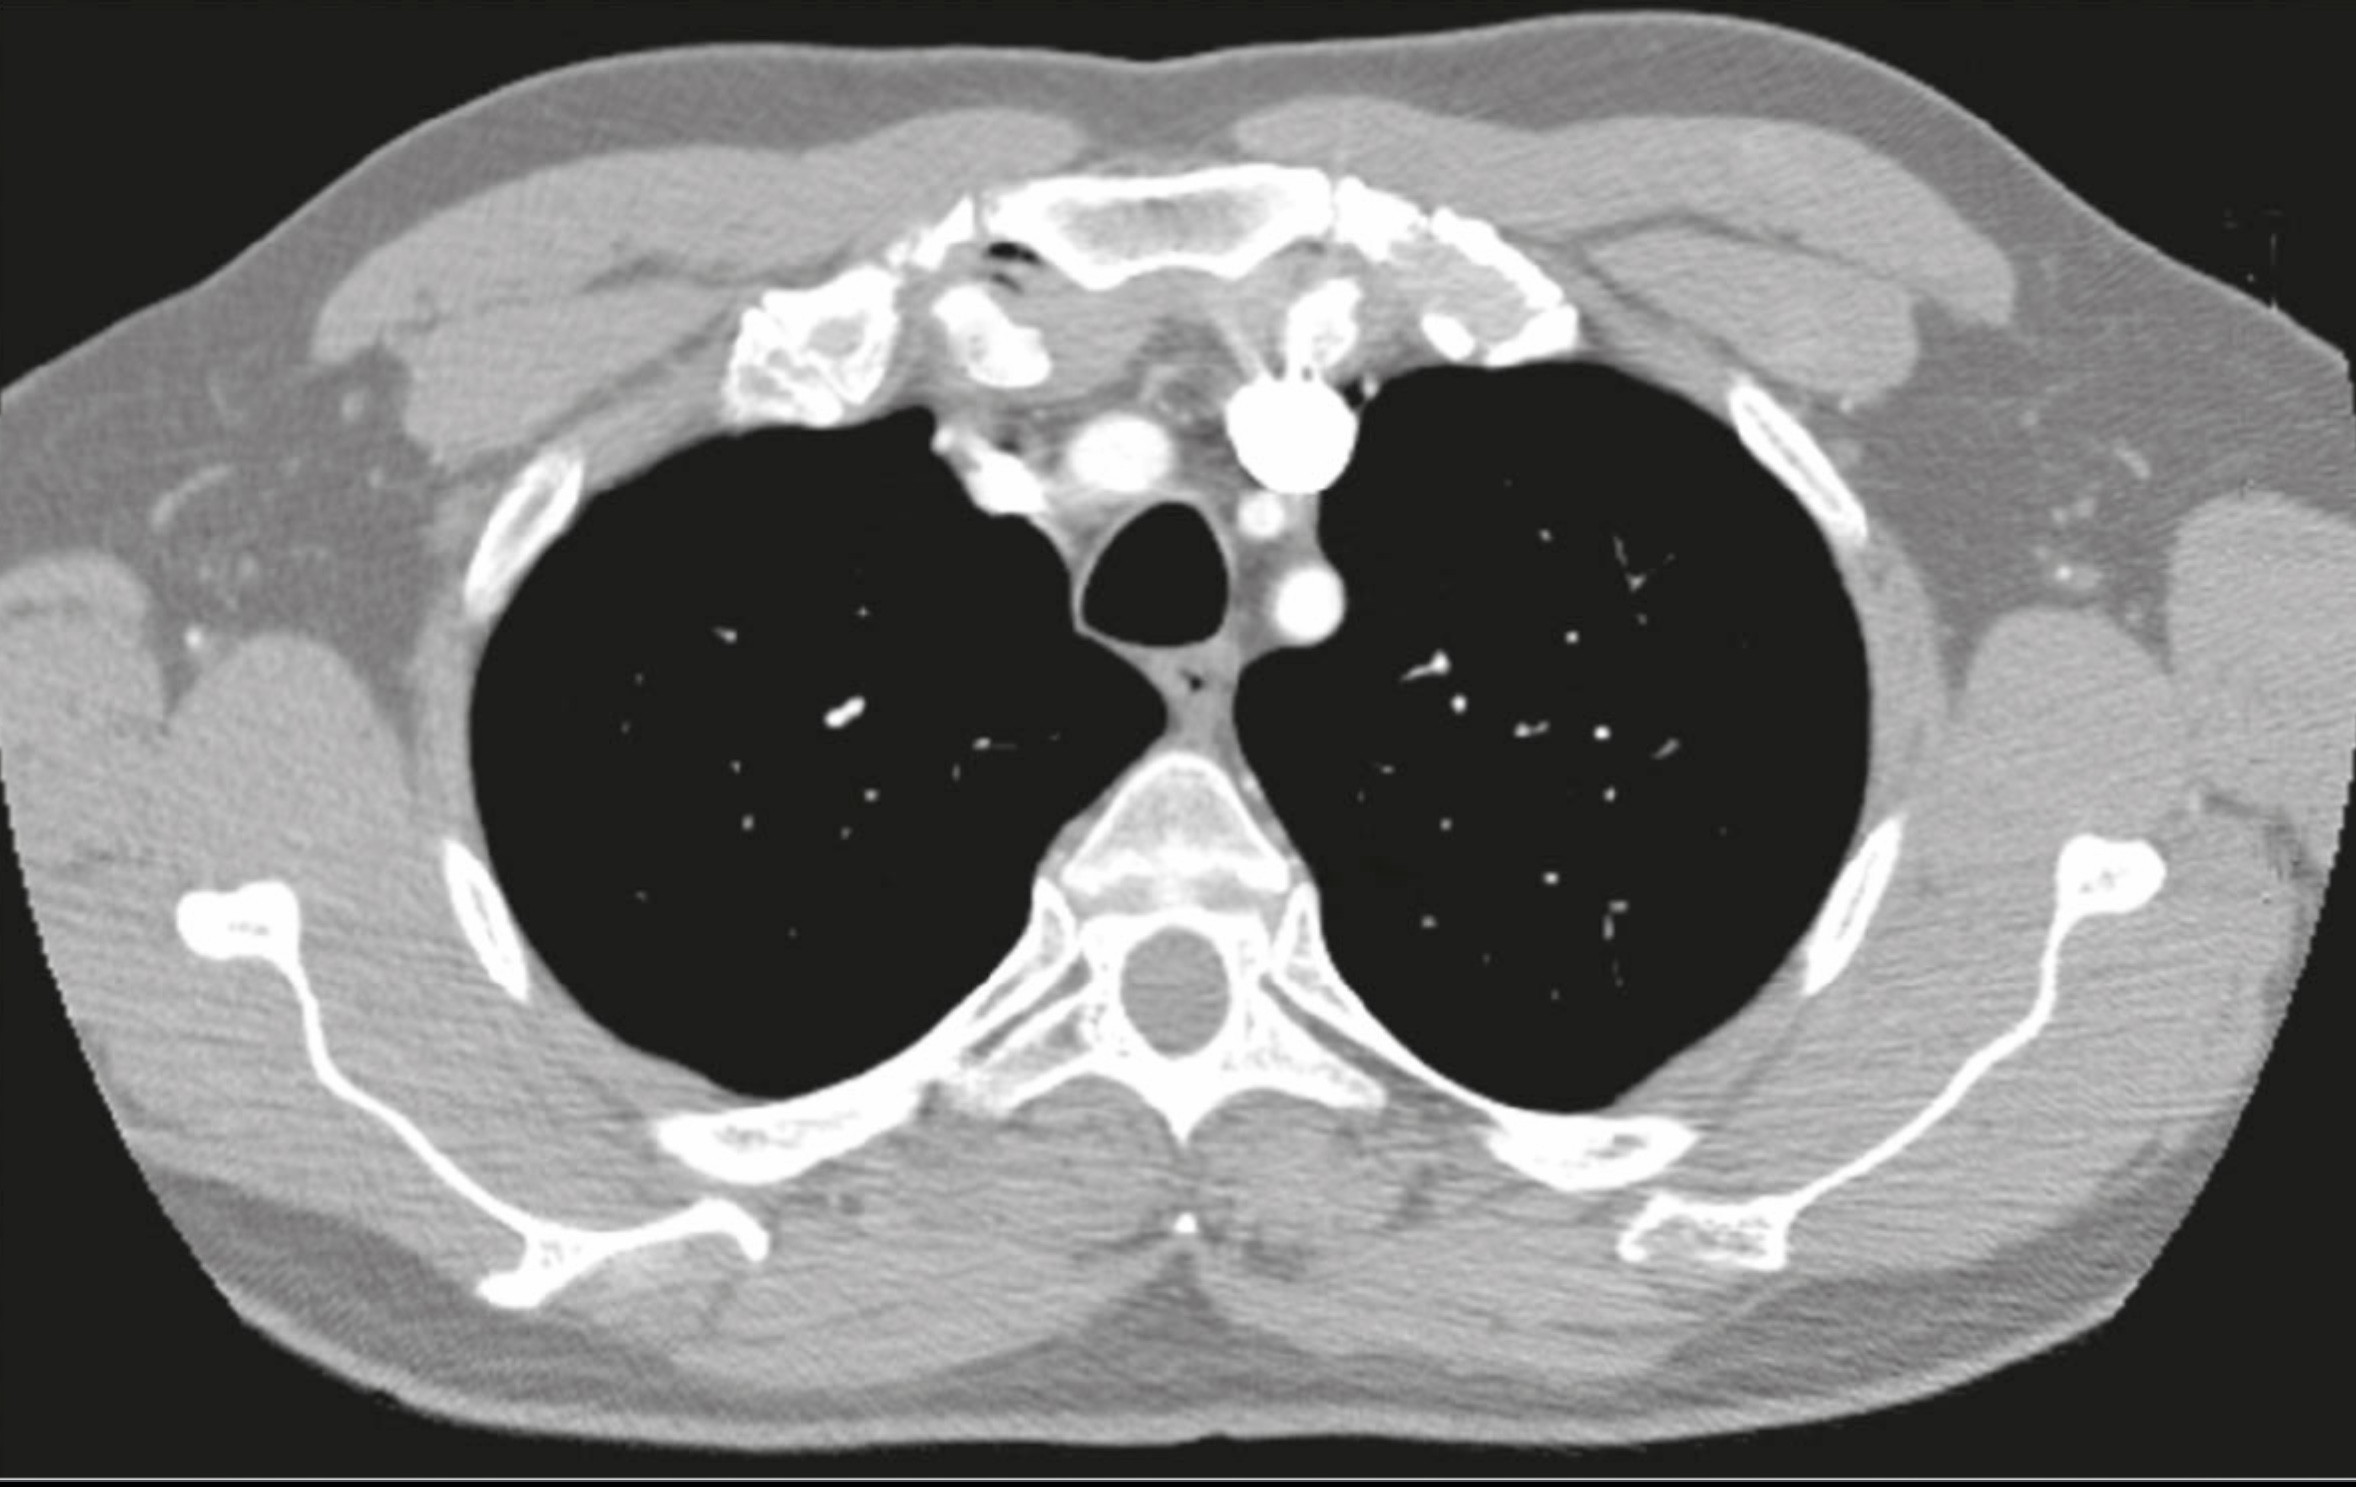

14. Coarctation of the aorta (narrowing or occlusion) in the region of ligamentum arteriosum limits delivery of blood to the descending aorta. (True)

15. Coarctation of the aorta changes the normal pattern of collateral circulation so that the posterior intercostal arteries supply retrograde blood flow to the descending aorta. (true)